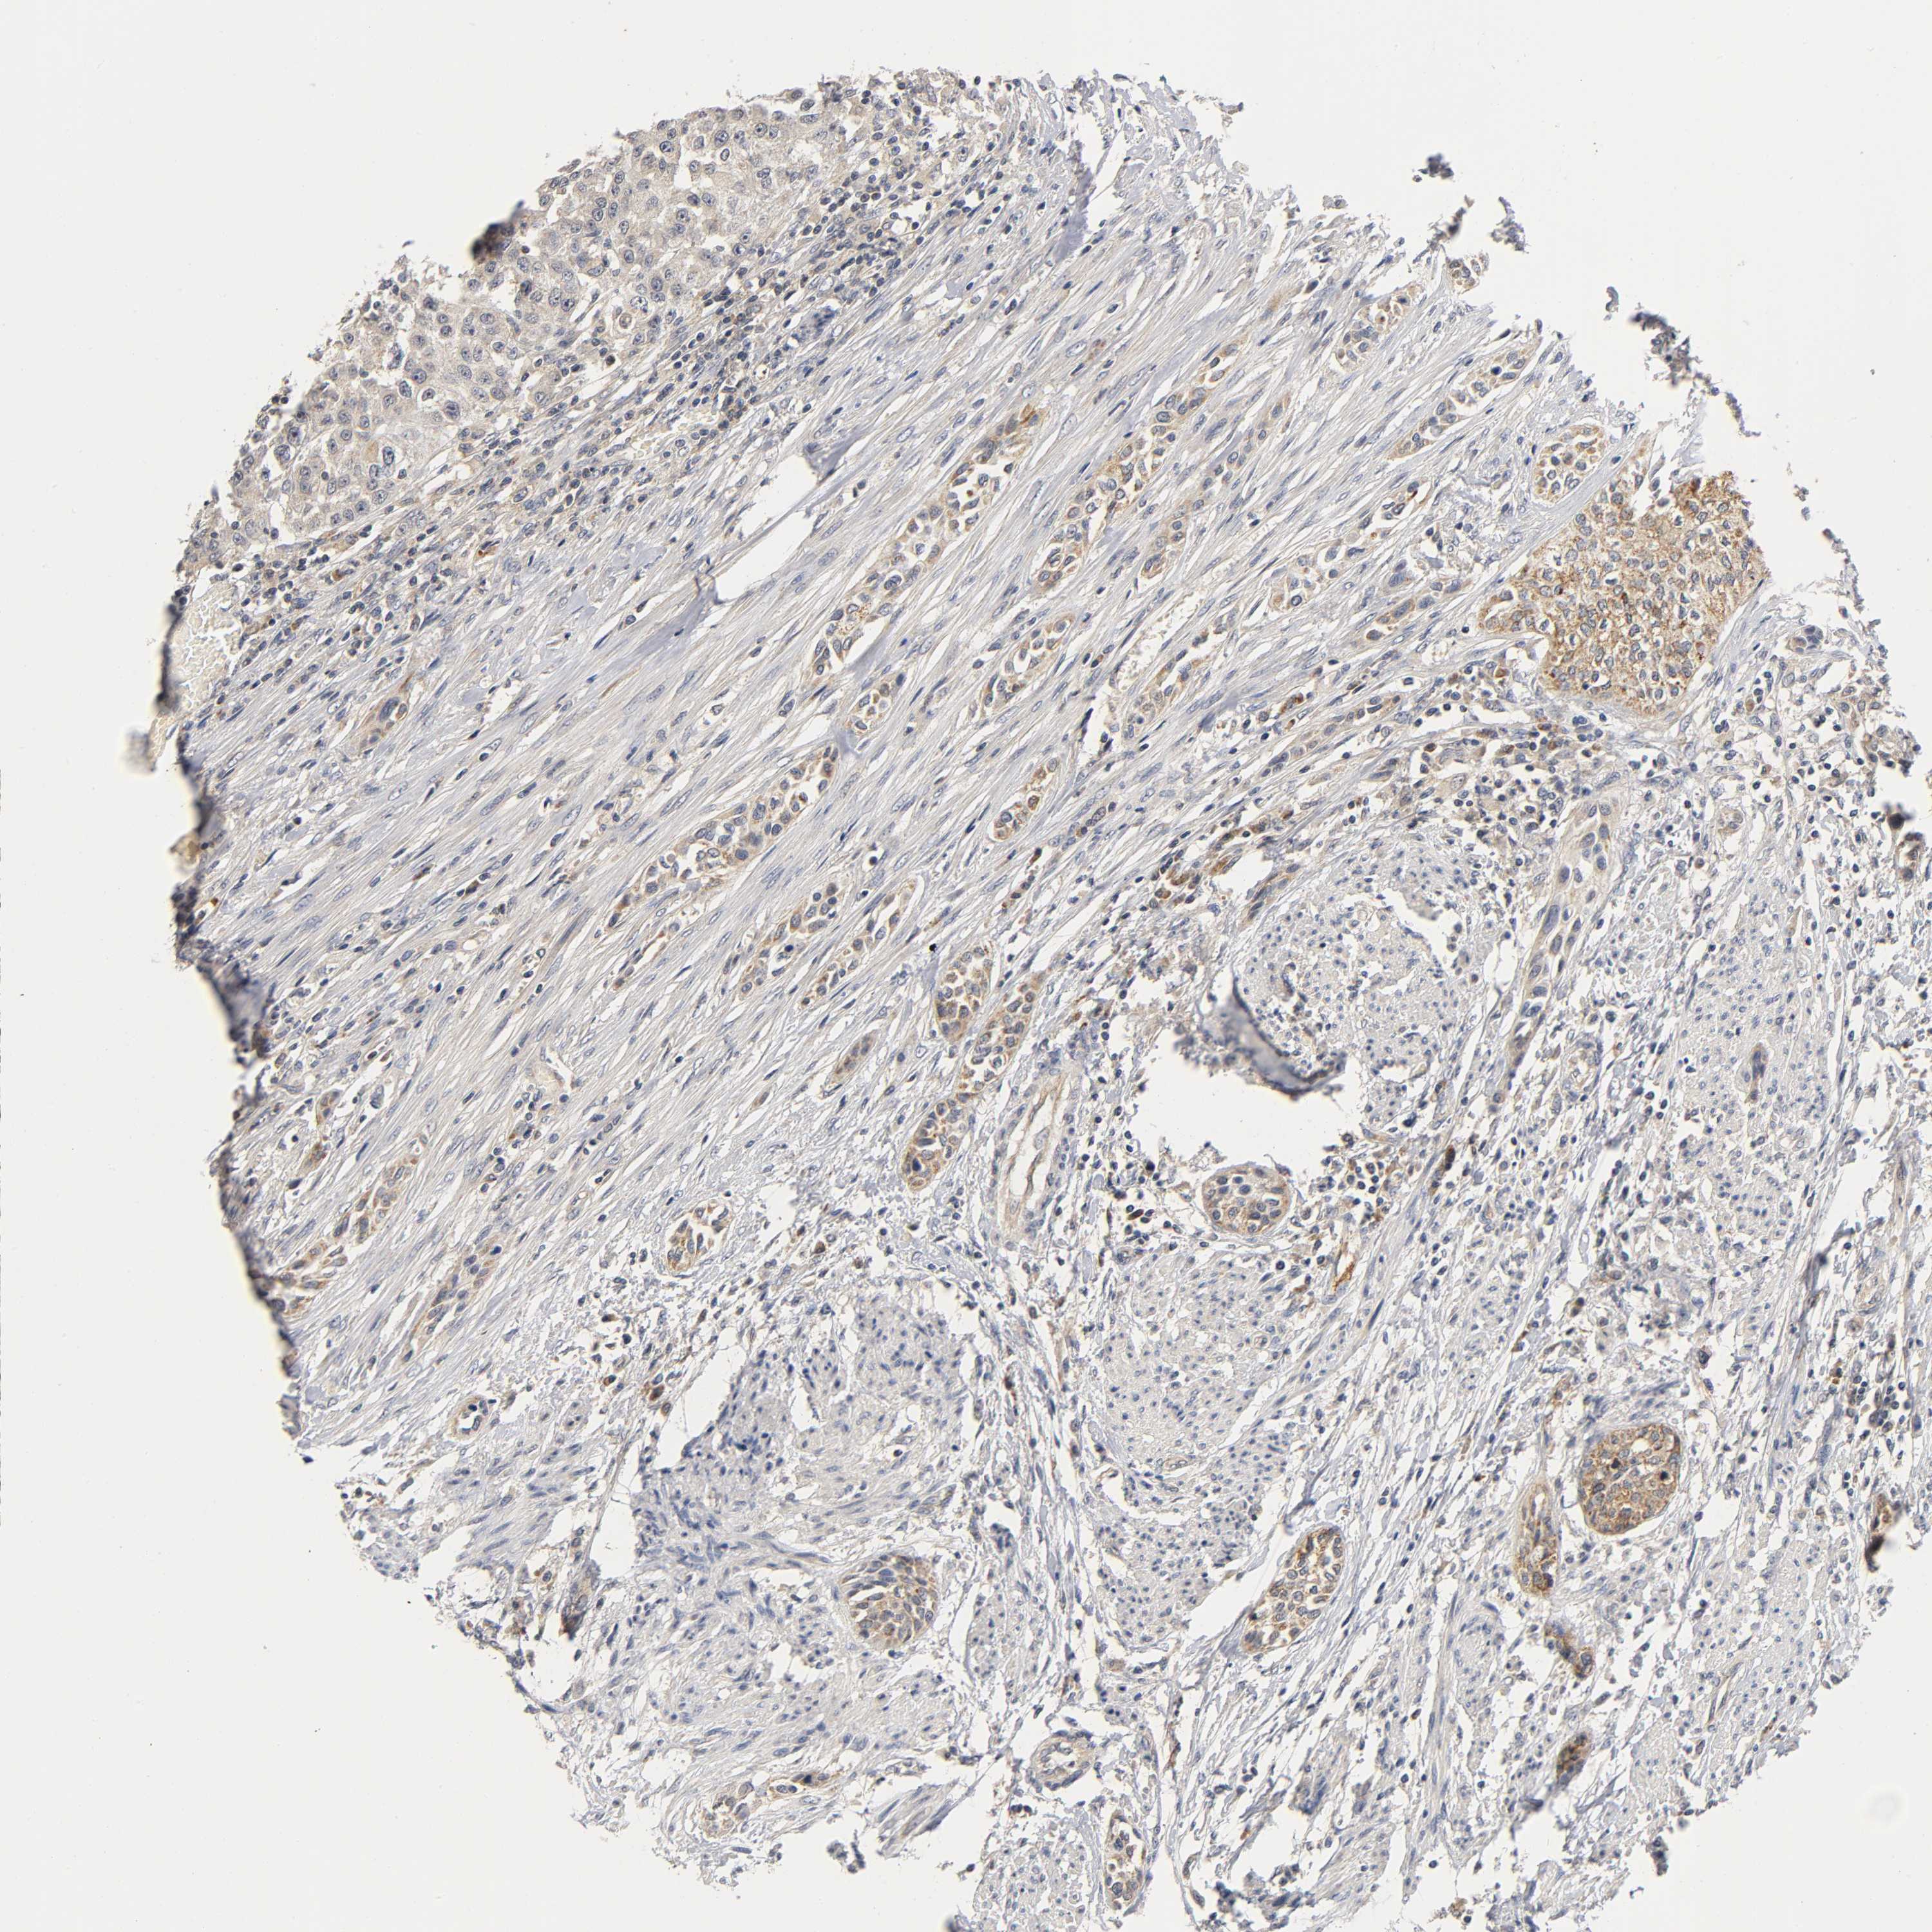

UROTHELIAL CANCER - Protein expressioni

A mouse-over function shows sample information and annotation data. Click on an image to view it in a full screen mode. Samples can be filtered based on level of antibody staining by selecting one or several of the following categories: high, medium, low and not detected. The assay and annotation is described here.

Antibody stainingi

Antibody staining in the annotated cell types in the current human tissue is reported as not detected, low, medium, or high, based on conventional immunohistochemistry profiling in selected tissues. This score is based on the combination of the staining intensity and fraction of stained cells.

Each image is clickable and will lead to virtual microscopy that enables deeper exploration of all samples and also displays staining intensity scores, fraction scores and subcellular localization as well as patient and tissue information for each sample.

Antibody HPA030278

Antibody CAB004511

Urothelial carcinoma, Low grade

Urothelial carcinoma, High grade